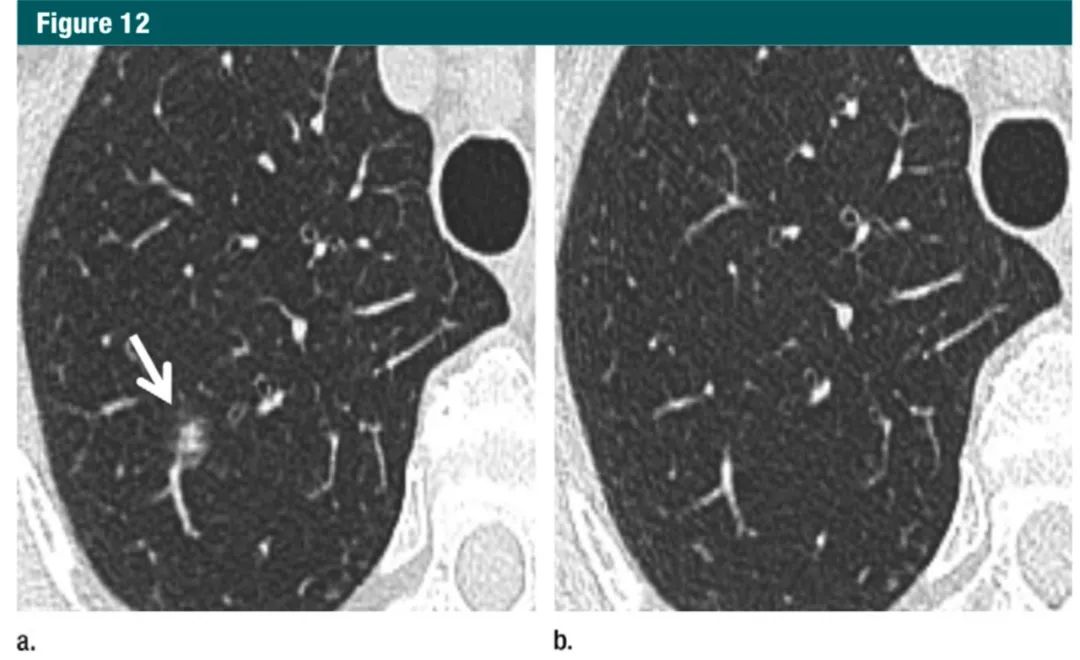

对于≥6mm 的孤立性部分实性结节,实性成分小于 6mm,建议随访时间是 3-6 个月,之后每年随访,最少 5 年。虽然部分实性结节的恶性可能性更高,但是实性成分<6mm 的结节常常表明是原位腺癌或微浸润性腺癌,而不是浸润性腺癌。另外,部分实性结节可能是短暂感染导致的,短期随访可能消失(图 12)。因此,建议最少随访一次(3-6 个月),以确定结节持续存在还是已经消失。对于持续存在的结节,建议每年随访,持续 5 年,以评估实性成分的稳定性。随访的终点定为5年似乎有点武断,但是对于部分实性结节的大小、CT 值 5 年后明确保持稳定的患者来说,这个时间(5 年)应该是合理的。

图12:a.横断位1mmCT层面,显示右肺上叶一个6mm的部分实性结节,实性成分<4mm(箭头);b.6个月后随访图像显示病灶完全消失,符合良性原因7Gc帝国网站管理系统